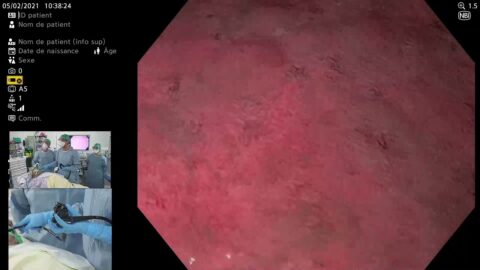

CONTRÔLE ET DESTRUCTION PAR CRYOABLATION DE L’ŒSOPHAGE DE BARRETT RESIDUEL